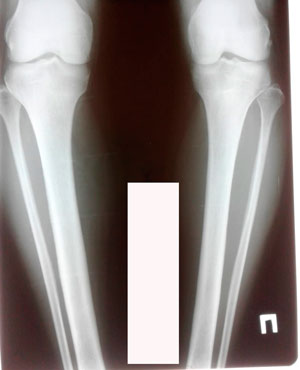

Исходник 38 лет.

Дата операции - 16.03.2020

Вложения

image-17-03-20-05-45-3.jpg

image-17-03-20-05-45-6.jpg